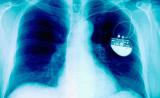

Изобретение немецких ученых может положить конец использованию кардиостимуляторов. Их технология применяет мягкие световые волны вместо электрического тока, которые вновь запускают остановившееся сердце...